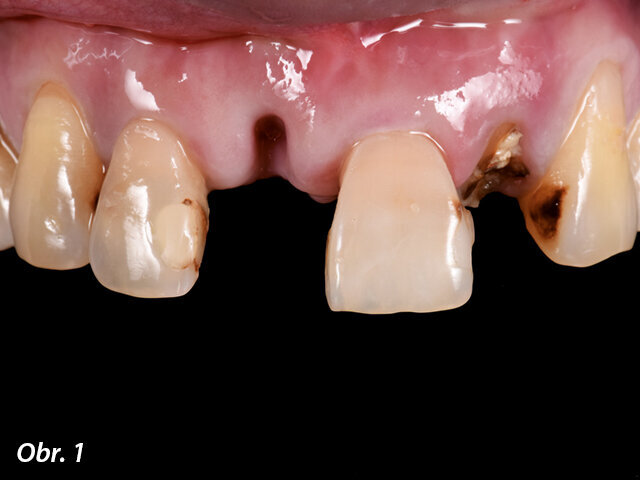

Na naše pracoviště se dostavila čtyřicetiletá pacientka, která před třemi týdny následkem synkopy utrpěla úraz horních frontálních zubů. Při klinickém vyšetření jsme diagnostikovali avulzi zubu 11 a korunky zubů 12 a 21 byly ulomené 3–5 mm pod úrovní gingivy s mobilitou III. stupně. Dále jsme zjistili zlomeninu korunky zubu 22 s lomnou linií končící ekvigingiválně. Ostatní zuby nevykazovaly žádné zjevné patologie či abnormality (obr. 1–4). Po vyloučení celkových onemocnění jsme se rozhodli pro ošetření pomocí implantátů s důrazem na estetiku a funkci.